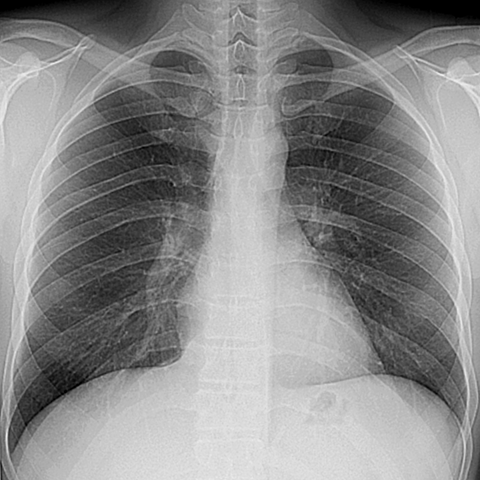

Normal PA Chest Radiograph [3 of 3]